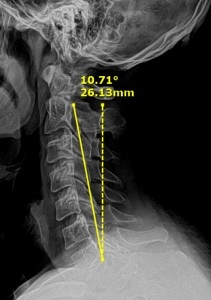

XRay Showing Neck Angle Before Chiropractic Care

50 year old male with an initial chief complaint of neck, shoulder and mid-back pain with a pain level of 5 out of 10. The patient finds difficulty in performing his job as a truck driver, reaching overhead and turning his head. Exam shows limited neck motion with pain in all directions, and a pinched nerve at C6 and T5. X-ray shows a loss of normal neck curve and a slumping posture. Treatment prescribed: 25 chiropractic adjustments, 12 deep tissue laser sessions, and 20 cervical decompression sessions.